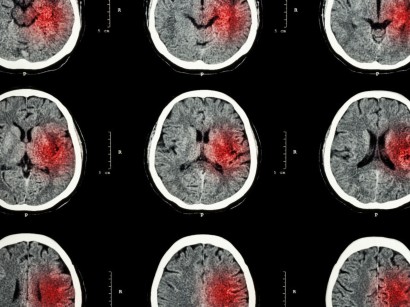

Hirnblutung 4 wochen nach sturz. Innerhalb des Hirngewebes oder zwischen Schädel und Hirn kommt es zu Blutungen die die Funktion der Hirnzellen beeinträchtigen. Lesen Sie mehr über die verschiedenen Formen von Hirnblutung ihre Symptome und Ursachen sowie Behandlung und Reha nach einer Gehirnblutung. So tückisch ist das Subduralhämatom Visite - 19.

Eine Gehirnblutung nach einem Sturz zum Beispiel beim Sport kann jederzeit auftreten. Bei einer subduralen Gehirnblutung nach Sturz handelt es sich um eine Blutung zwischen der harten Hirnhaut und der sogenannten Spinngewebshaut. Dies ist nun genau 5 Wochen her.

Wie lange es nach Kopfverletzungen mit Hirnblutung dauert bis die Betroffenen wieder völlig hergestellt sind hängt von Ausmass und Art der Verletzungen ab. Meist wird sie von Betroffenen nicht ernst genommen sodass kein Arztbesuch erfolgt. Wie erkennt und behandelt man eine Hirnblutung.